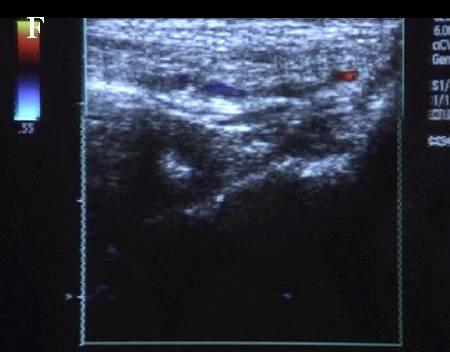

A 连接三联管及穿刺针准备 B 超声引导下注射针进入瘤腔底部(箭头处) C 经注射针注入盐水出现超声频闪现象; D 远端瘤腔内血栓逐渐形成; E 远端、近端瘤腔内血栓完全形成; F 术后足背动脉血流良好. 国内首家开展,例数最多,疗效肯定。此技术在全国推广应用。处于全国领先水平。